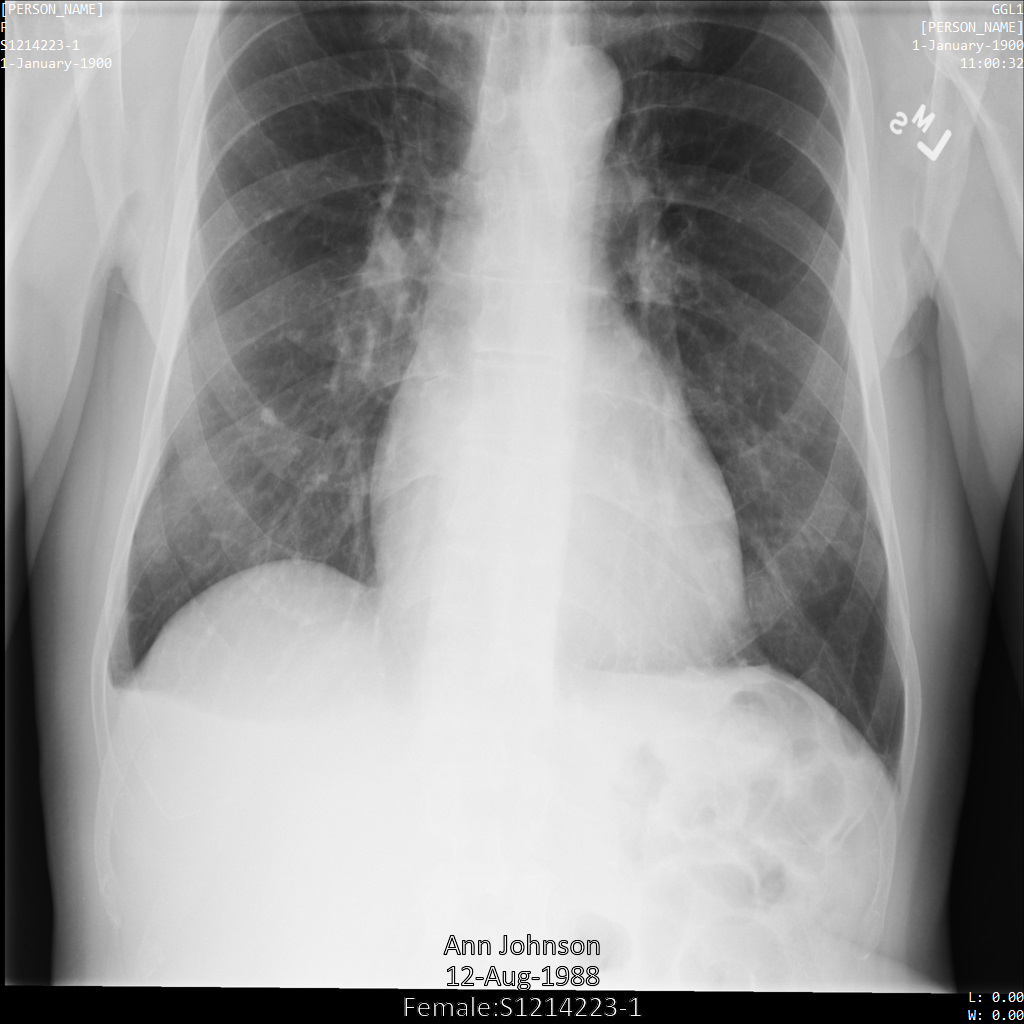

L'image suivante montre une radiographie non masquée d'un patient :

Une fois l'image envoyée à l'API Cloud Healthcare à l'aide de l'option REDACT_SENSITIVE_TEXT, elle apparaît comme suit :

Vous pouvez constater que les événements suivants se sont produits :

- Le paramètre

PERSON_NAMEen bas à gauche de l'image a été masqué. - Le paramètre

DATEen bas à gauche de l'image a été masqué.

Le sexe du patient n'a pas été masqué, car il n'est pas considéré comme du texte sensible selon le paramètre infoTypes DICOM par défaut.